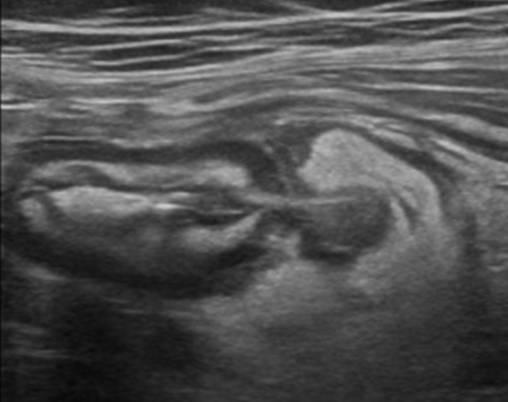

Viêm túi thừa

» Thông tin: Nam giới – 66 tuổi.

» Lâm sàng: Đau hố chậu trái / Sốt.